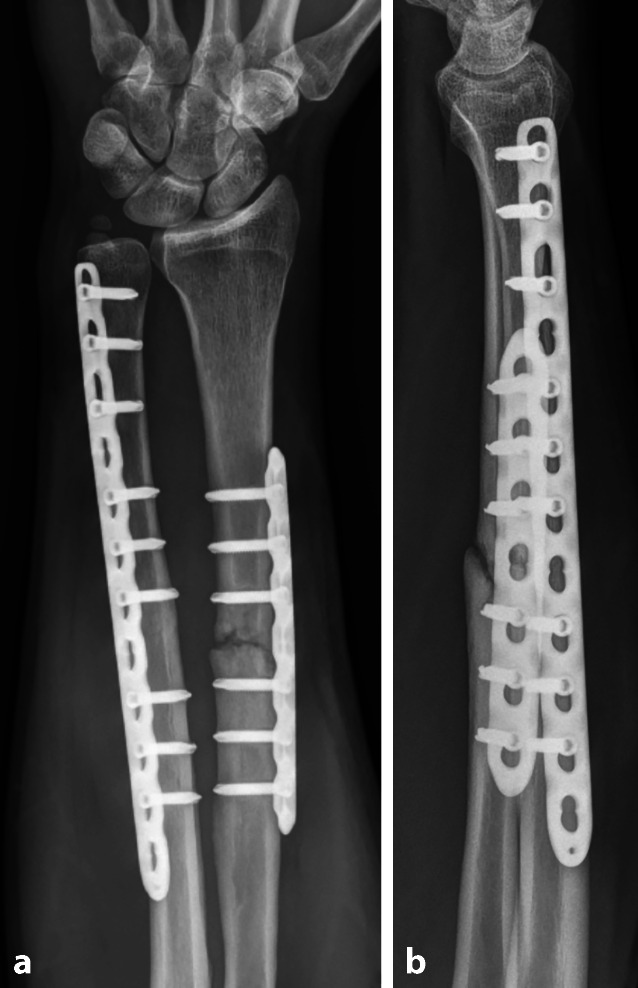

The management of shaft fractures of the upper extremities is an integral part of trauma surgery in the clinical routine. While sport-associated injuries predominate in young adults, the incidence of osteoporotic fractures greatly increases in older patients. Despite established treatment strategies, complications such as wound healing disorders, infections, neurovascular injuries, malalignment, pseudarthrosis and implant failure are frequent. An effective complication management requires detailed knowledge of the morphological features of fractures, individual risk factors and differentiated revision strategies. With the presentation of two clinical cases, we aim to highlight the necessity of individualized treatment concepts. Due to the increasing number of war casualties transferred for secondary treatment to Central Europe, the likelihood of encountering unfamiliar injury patterns, such as blast or gunshot wounds, is rising. This development presents new challenges in daily clinical practice. Physiotherapeutic and occupational therapy support play a central role in achieving favorable functional outcomes following revision surgery for diaphyseal fractures of the upper extremities. In geriatric care, orthogeriatric concepts have significantly decreased mortality and improved mobilization as well as self-sufficiency among older patients. Managing patient expectations and providing close supervision throughout the rehabilitation process are decisive factors for successful recovery.

Abstract Image